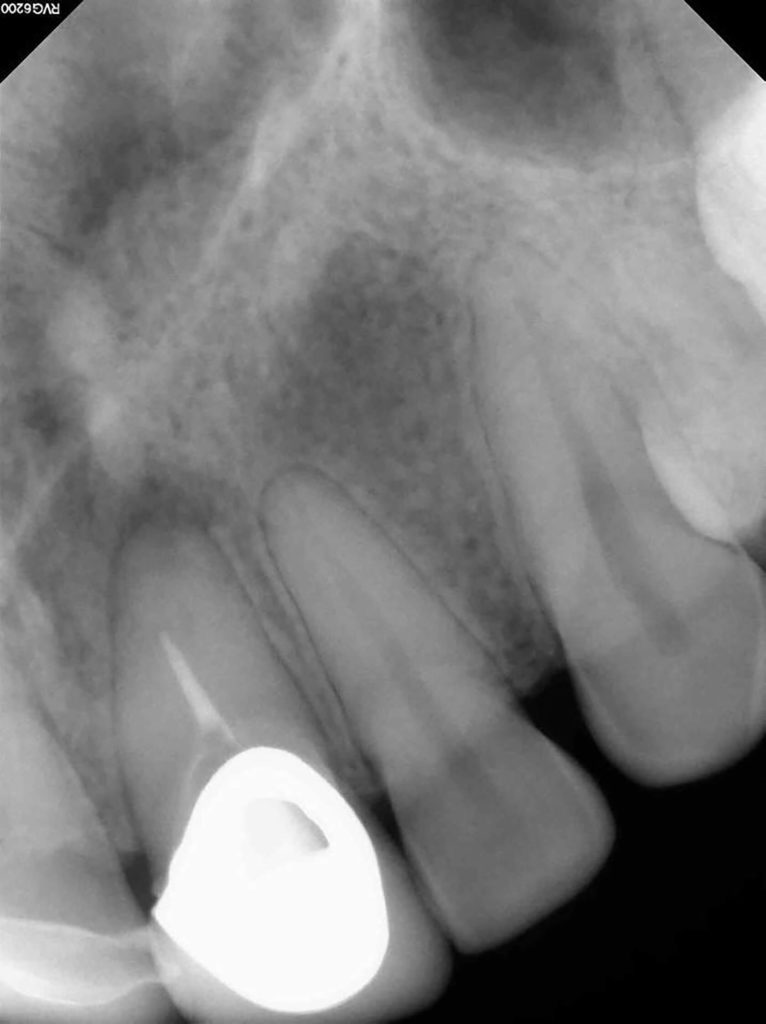

Fun retreatment. Patient had RCT on 9, which was retreated by another endodontist 5 years ago. Patient developed pain and swelling in the area. CBCT revealed a transported canal with a perforation. I was able to locate the canal and hopefully save the tooth!